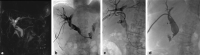

Biliary endoscopy is underutilized by interventional radiologists and has the potential to become an effective adjunctive tool to help both diagnose and treat a variety of biliary pathology. This is particularly true in cases where endoscopic retrograde cholangiopancreatography fails or is not feasible due to surgically altered anatomy. Both preoperative clinical and technical procedural factors must be taken into consideration prior to intervention. In this article, clinical evaluation, perioperative management, and procedural techniques for percutaneous biliary endoscopy are reviewed.